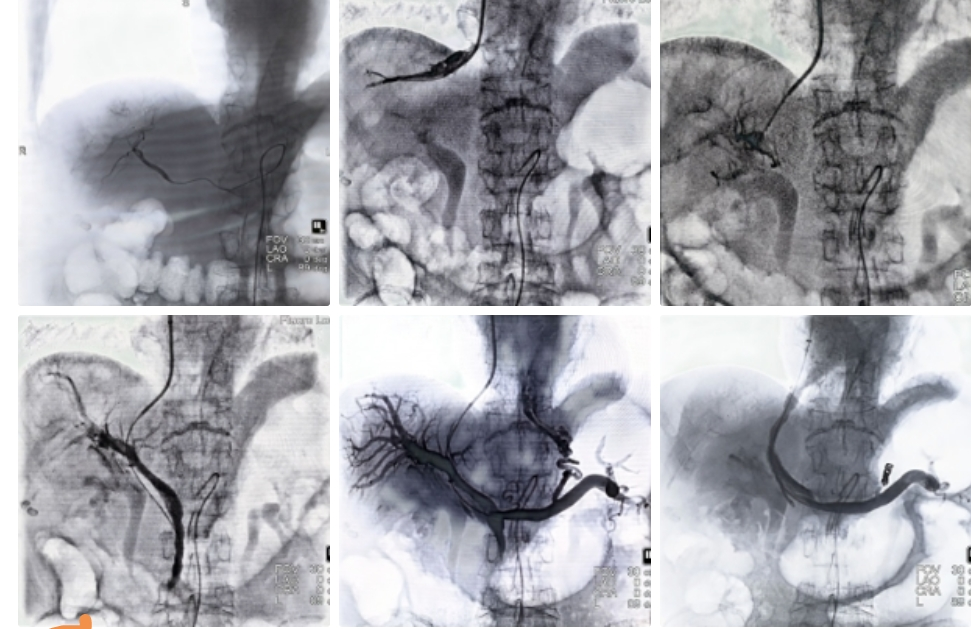

4月9日,我院消化疾病临床诊疗中心消化肝病专业组为一名71岁肝恶性肿瘤伴门脉高压静脉曲张破裂出血的患者实施“双介入”手术。该患者一月前诊断“肝恶性肿瘤”,此次因突然大量呕血入院,在完善急诊胃镜及腹部增强CT,与家属谈话后决定为患者实施“双介入”联合治疗,即经导管肝动脉栓塞术(TACE)协同经颈静脉肝内门体分流术(TIPS)。术中通过术前增强CT指导术中精准穿刺门静脉左支并建立分流道进行“降压”,考虑到患者属于肝脏储备功能较差的患者人群,术中对分流道进行了亚扩张限流;同时行肝动脉造影并栓塞肿瘤供血分支血管进行“控瘤”。术后第二天患者即恢复进食,目前患者病情已趋于稳定并即将出院。

肝动脉栓塞“控瘤”,TIPS术分流降压并栓塞侧枝循环静脉“止血”